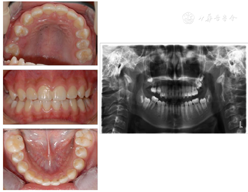

患者,女性,11岁,2018年3月以"右下后牙区囊肿及右上后牙残根2月余"为主诉就诊。患者约2年前治疗口内多颗坏牙,45行根管治疗,16行充填治疗,治疗后未定期复查,16牙冠逐渐脱落,于外院拍片检查发现16残根,右下后牙区囊肿。患者既往体检,无全身病史,父母均健康,无类似病史。检查见:16残根,近远中边缘深达龈下2~3 mm,颊舌边缘位于龈上1.0~1.5 mm,大量腐质。15,17未萌出,46和44之间间隙约2 mm(图1)。曲面断层片显示:16残根,根尖区见低密度影,15阻生,牙根发育Nolla 8期,17牙根发育Nolla 7期,18牙根发育Nolla 5期(图2)。44-46颊侧牙槽骨膨隆,质地硬,无压痛,未及波动感,85远中及牙合面大面积充填体,边缘欠密合,不松动。曲面断层片显示:85牙根大部分吸收,远中根剩余约1mm,根管内见根充影像,45牙轴偏向远中,牙根发育Nolla 8期,44远中至46近中范围可见大面积低密度影,边缘清晰,包绕于45牙颈部。CBCT显示:低密度影近卵圆形,大小约为1.0 cm×1.2 cm×1.4 mm,边界清楚,颊侧骨板薄(图3)。

曲面断层片显示:85牙根大部分吸收,右侧下颌后牙区见大面积低密度影像,边缘清晰,包绕于45牙颈部。15阻生,牙根发育Nolla 8期,17、18牙胚存。CT检查显示:右下后牙区骨密度减低区域大小约为1.0 cm×1.2 cm×1.4 mm,颊侧骨板薄。